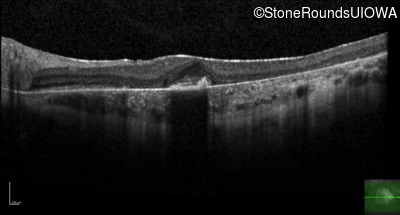

Age at visit: 30 years

This 30 year old man first noticed poor vision in dim light when he was five years old. His visual acuity began to fall in his early 20's.

Age at visit: 34 years

Macular Disease WDR19 His344Arg CAT>CGT Ser485Ile AGT>ATT AR